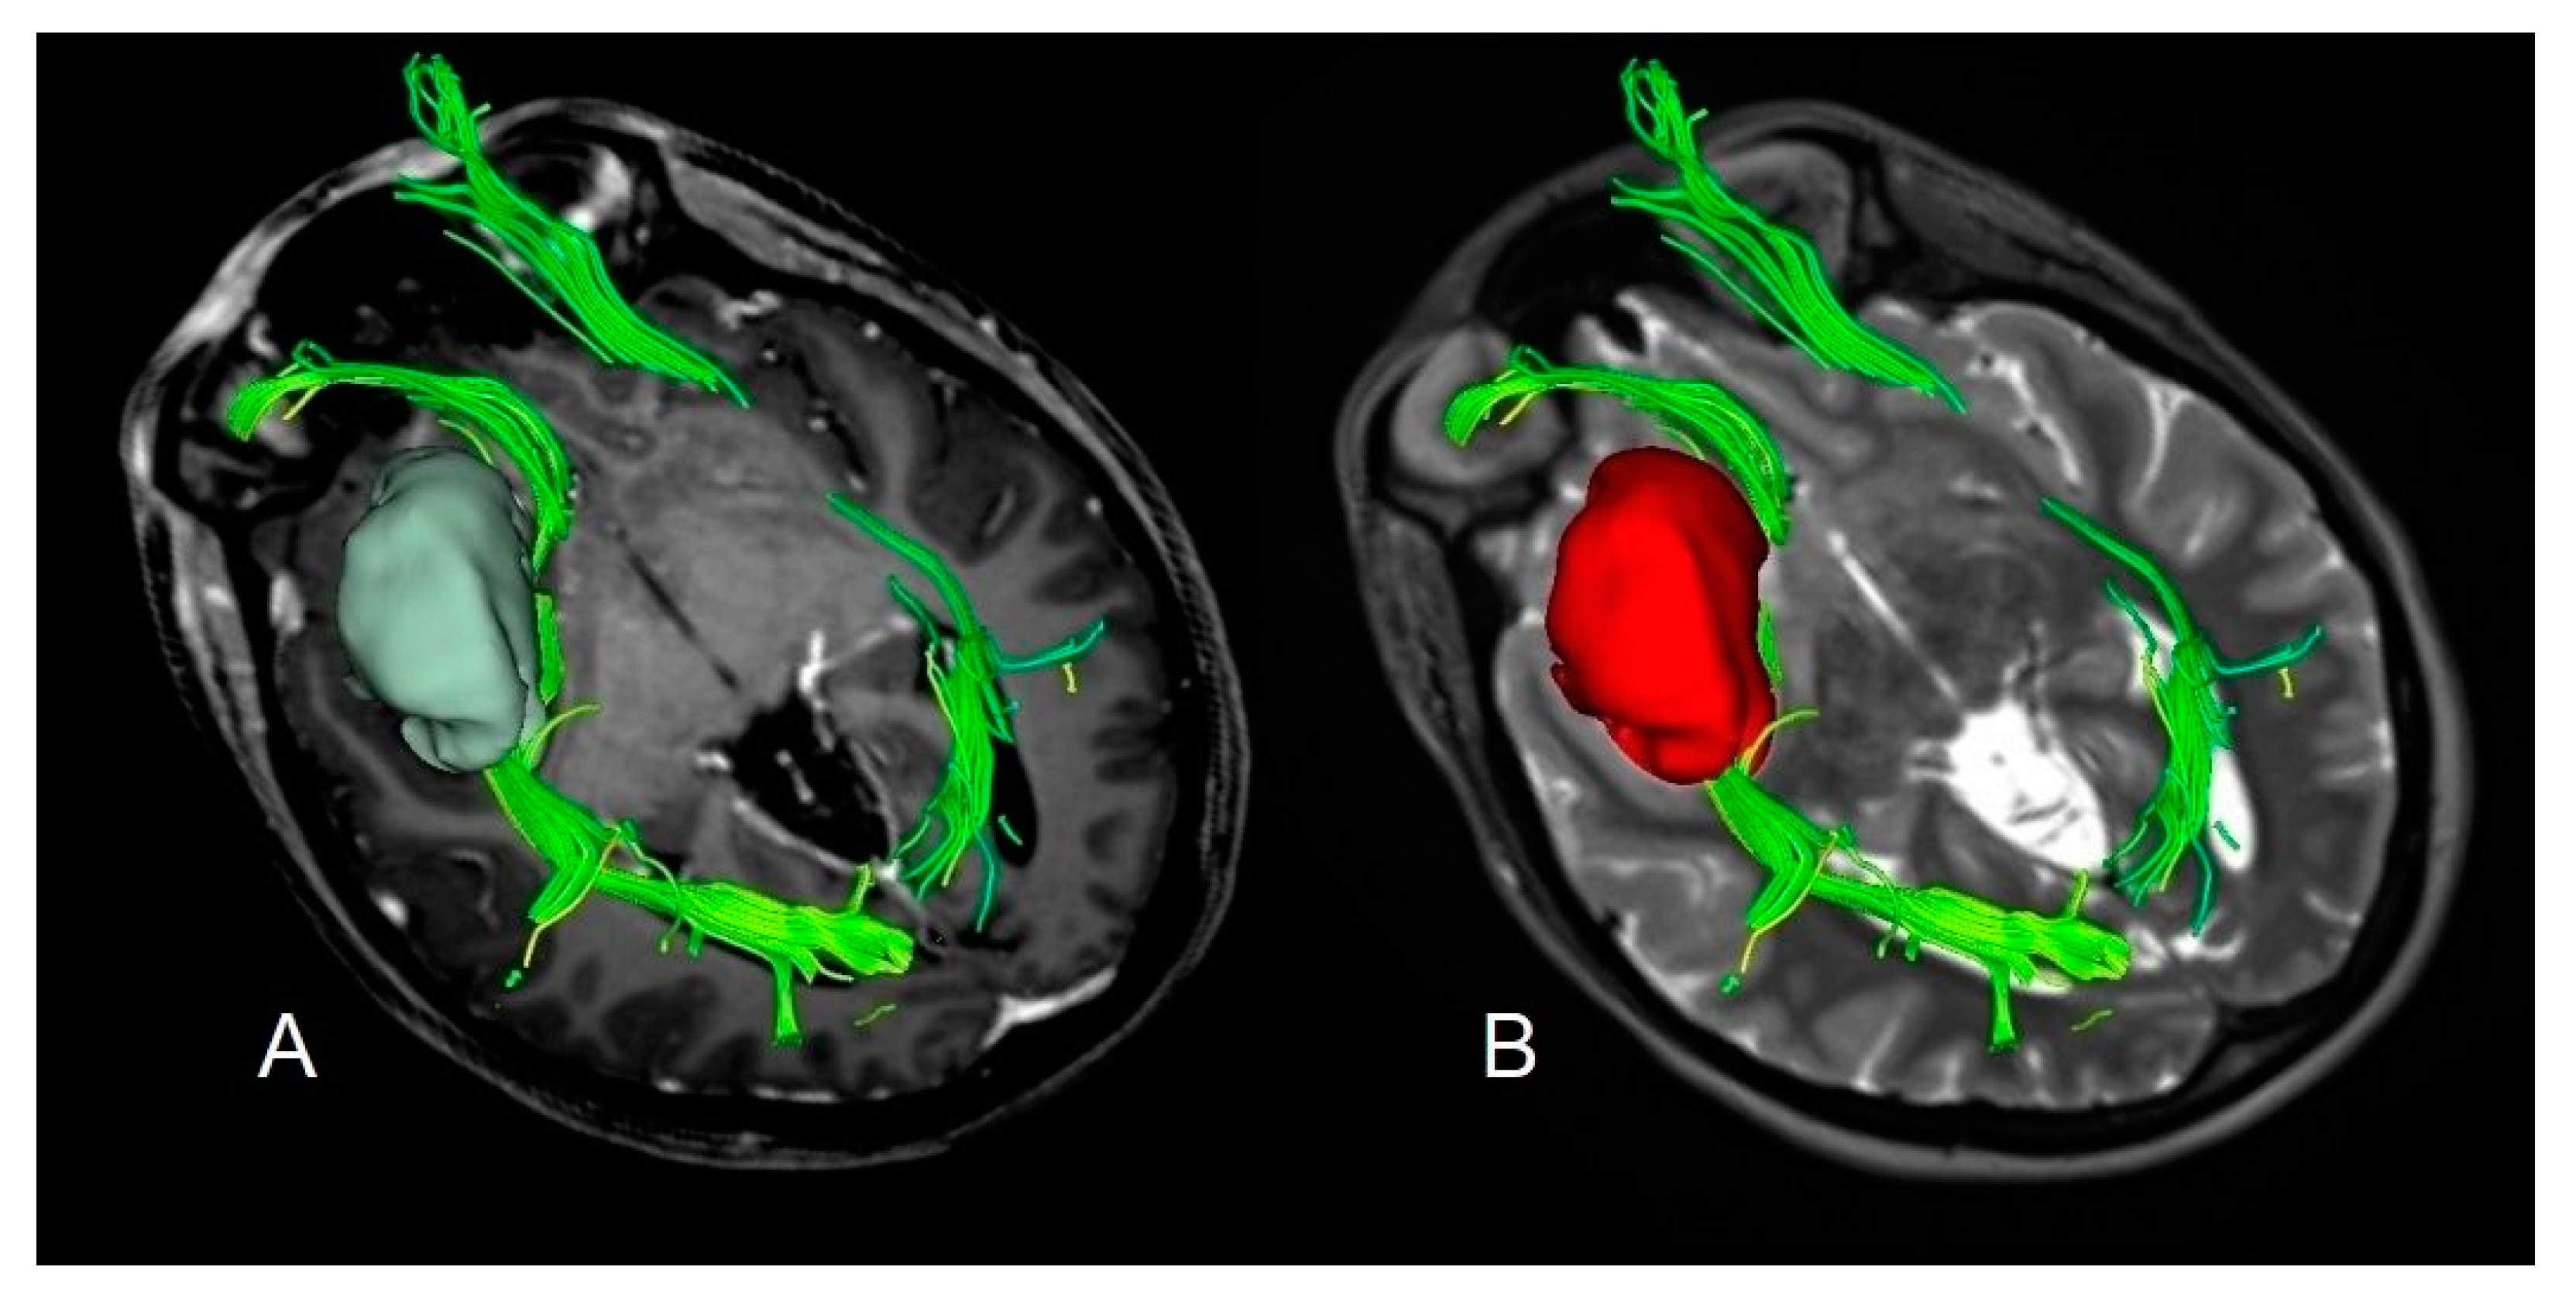

4.3. Volumetric Analysis